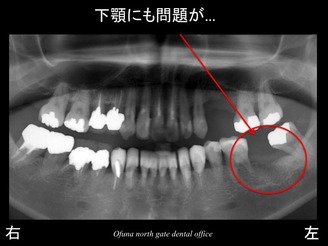

次に下顎左側の奥歯にも問題がありました。

下顎も骨吸収の状態を見てみましょう。

骨吸収以上に問題があったのが、下顎神経の存在です。

下の顎には、下顎神経という太い神経の管があります。

この下顎神経の位置は、上方にあったり、下方にあったりと 個人差があります。

この患者様の場合、かなり上方にあったのです。

下顎は、

骨吸収がある!

下顎神経が上方にある!

という2点から インプラントを埋入する長さに制限がありました。